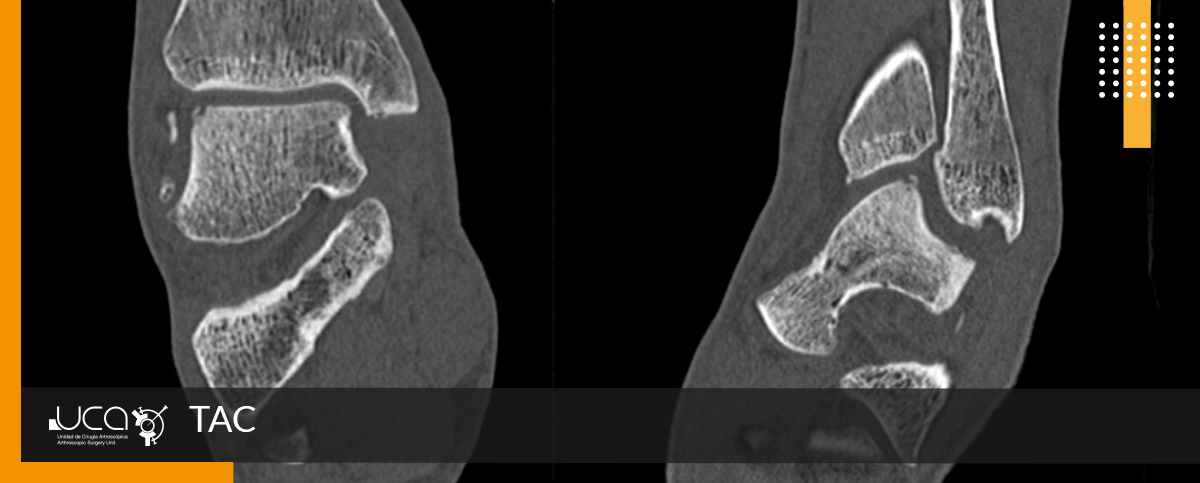

El TAC nos muestra una mínima lesión osteocondral en vertiente externa de cúpula astragalina con pequeño fragmento óseo no desplazado.